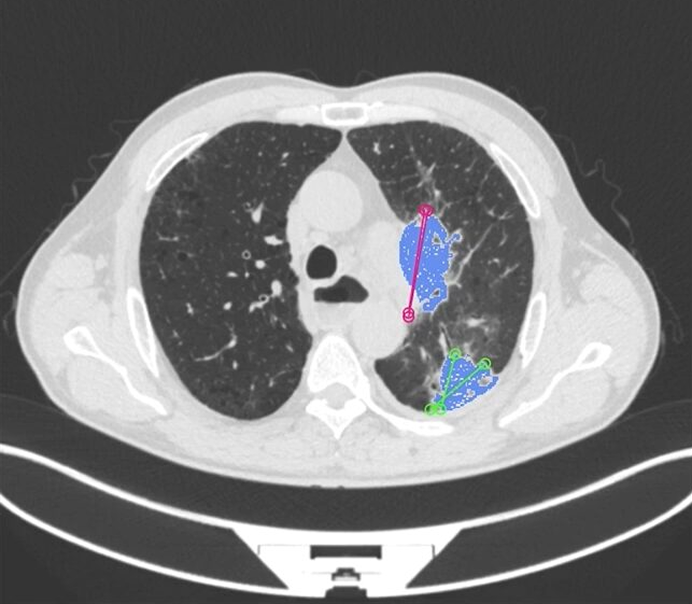

1. Tumor Detection and Delineation

Segmentation allows AI to precisely outline tumor boundaries, differentiate solid vs. necrotic regions, and track volumetric changes over time. This enhances diagnostic confidence, improves treatment planning, and supports personalized radiotherapy dose optimization.

9. Radiomics Feature Extraction

Segmentation defines the exact boundaries for extracting radiomic features related to intensity, texture, shape, and heterogeneity. These features power predictive models for prognosis, treatment response, risk scoring, and precision-medicine workflows.